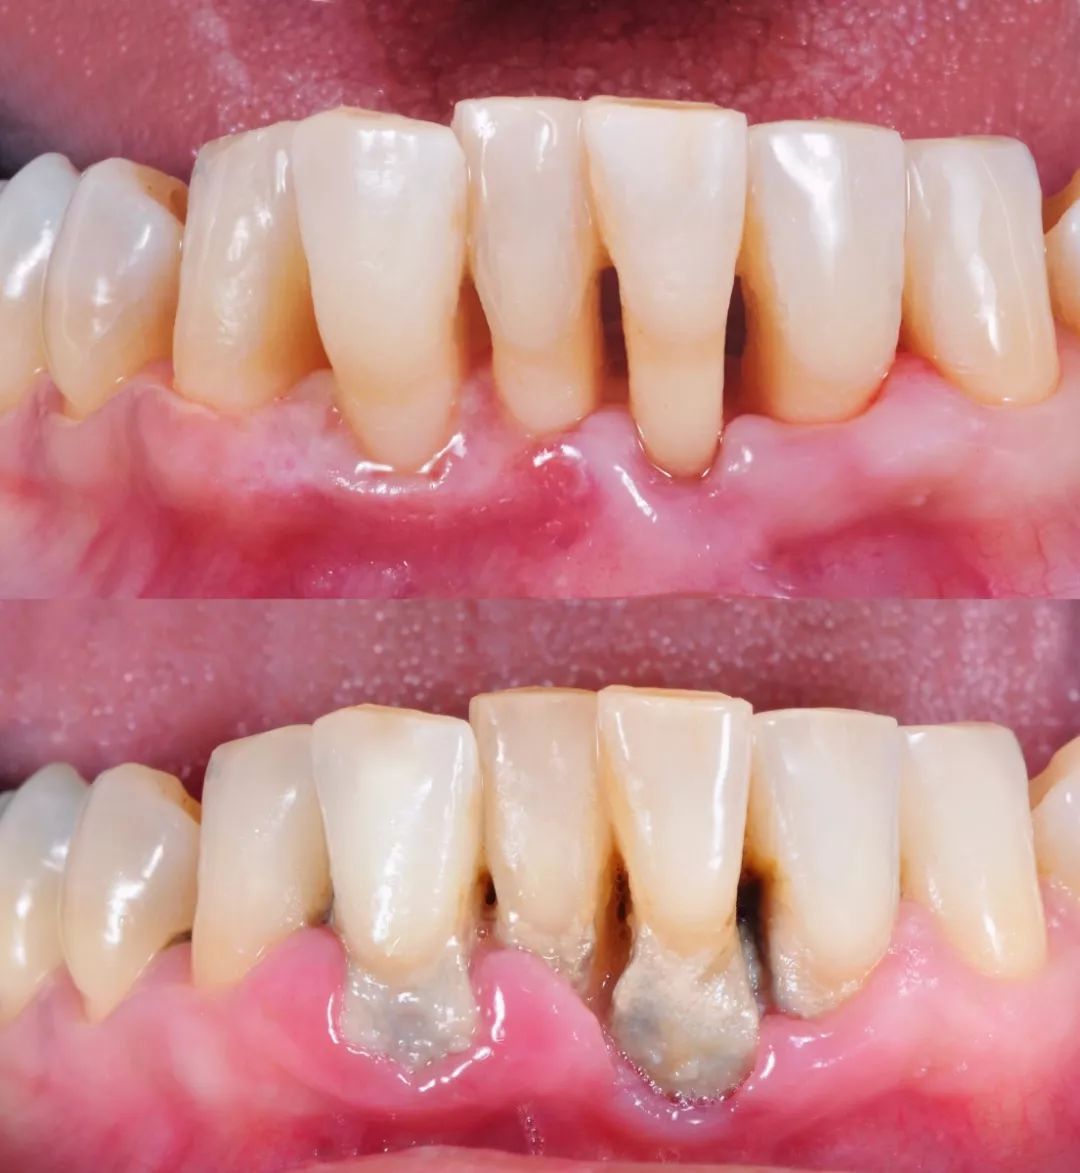

Prevention and Treatment of Gingival Diseases: Effectively controls gingivitis and periodontitis, reducing problems like gingival bleeding and halitosis (bad breath) .

Maintenance of Alveolar Bone Health: By controlling inflammation, it helps maintain the height of the alveolar bone, preventing tooth loosening and loss .

This is a dangerous misunderstanding. Periodontal diseases often have no obvious symptoms in their early stages . By the time bleeding, swelling, pain, or tooth mobility occur, the damage is often irreversible. Regular professional cleaning is a preventive, not just a treatment, measure – much like a physical examination .